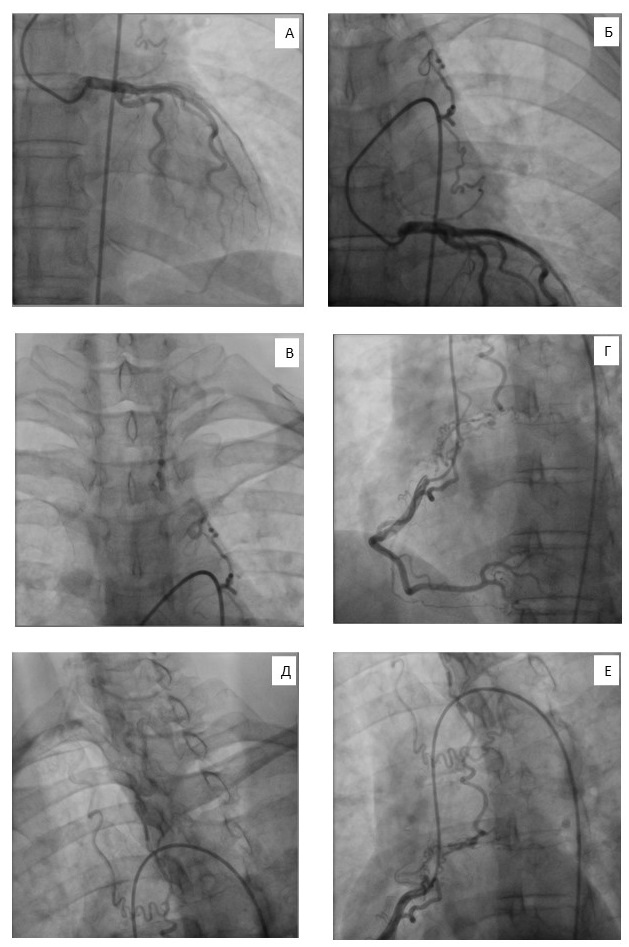

Coronary angiography and angiography of the aortic arch branches did not reveal any significant stenosis of coronary arteries. However, there were verified occlusion of the BCT, right CCA, left CCA, right ICA and left ICA; 85% stenosis in the first segment of the left SA and 80% stenosis of the left vertebral artery; collaterals between the left vertebral artery and systems of the left coronary artery (LCA) and right coronary artery (RCA, Figure 2).

Fig. 2. Angiograms of the patient demonstrating collateral circulation between the system of the right and left coronary arteries and left vertebral artery: collaterals between the left coronary artery and left vertebral artery (A, B, C); collaterals between the right coronary artery and left vertebral artery (D, E, F).